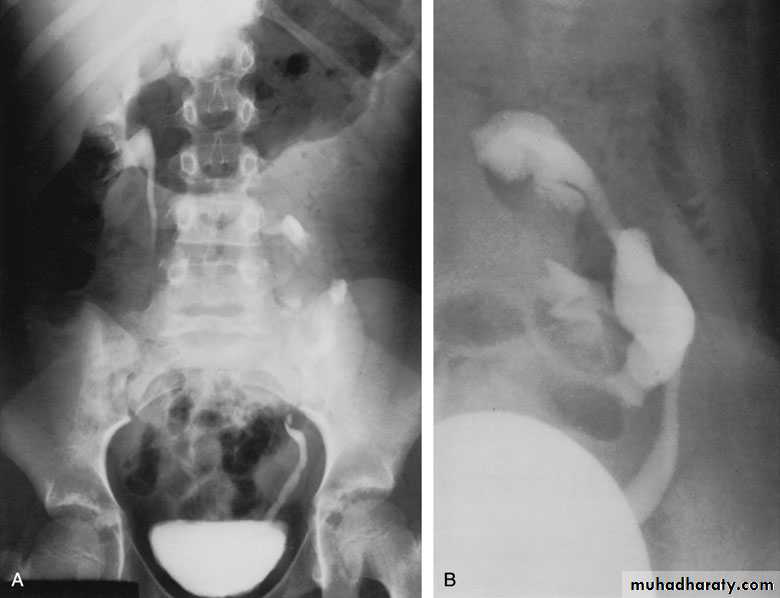

Ureteropelvic Junction (UPJ)(PUJ) Obstruction (stenosis)

The most common cause of significant dilation of the collecting system in the fetal kidney

Boys > Girls

Left-sided lesions predominate

15% bilateral

DIAGNOSIS

U/S: hydronephrosis

IVU: diagnostic , hydronephrosis with

fixed stenotic segment or complete

obstruction

CT scan: hydronephrosis that ends

abruptly